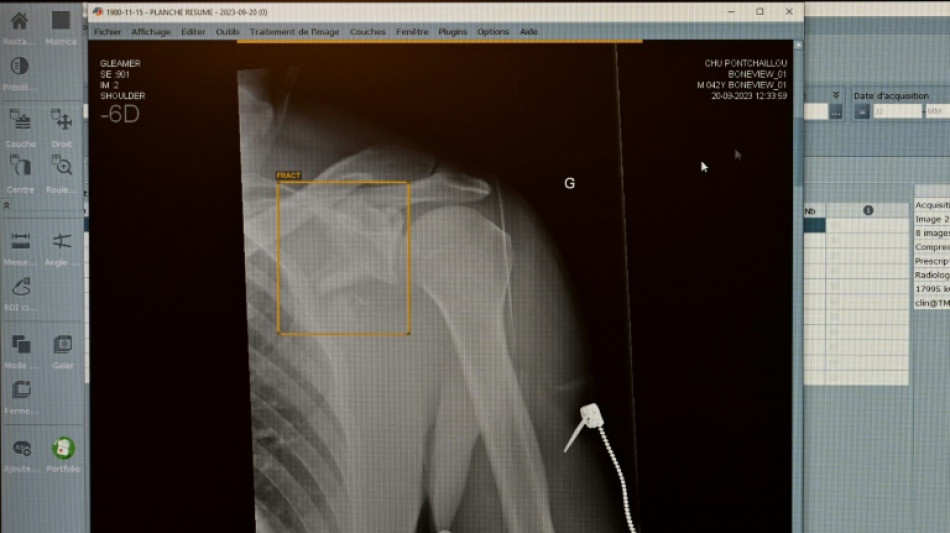

TÜV-Verband: Weniger Röntgengeräte mit Mängeln - Risiken bleiben aber

Jedes achte vom TÜV im vergangenen Jahr geprüfte medizinische Röntgengerät hat Mängel aufgewiesen. Die Gutachter stellten an 1893 der insgesamt rund 15.600 untersuchten Röntgengeräte Mängel wie etwa unzureichend gekennzeichnete Kontrollbereiche fest, wie der TÜV-Verband am Mittwoch in Berlin mitteilte. Die höchste Mängelquote wiesen Röntgengeräte in Zahnarztpraxen auf.

Insgesamt sank der Anteil der festgestellten Mängel im Vergleich zum Vorjahr aber von 16 Prozent auf zwölf Prozent. Dennoch fanden die TÜV-Gutachter 2849 einzelne Mängel. "Röntgenstrahlung ist niemals harmlos", erklärte Alexander Schröer, Strahlenschutzexperte des TÜV-Verbands. Geräte müssten daher nicht nur technisch einwandfrei funktionieren, sondern auch korrekt betrieben werden, "um die Strahlenbelastung für Patienten und medizinisches Personal zu minimieren".

Als "besorgniserregend" bezeichnete es der Prüfverband, dass jeder fünfte Mangel (19 Prozent) in die Kategorie der schwerwiegenden Mängel falle. Solche Geräte dürfen erst nach der Beseitigung der Mängel und einer neuerlichen Prüfung wieder in Betrieb gehen.

Gut jedes zweite (54 Prozent) der 2024 geprüften Röntgengeräte entfällt demnach auf die Zahnmedizin. 15 Prozent davon wiesen mindestens einen Mangel auf. Am häufigsten fielen ein mangelhafter Patientenschutz und unzureichend gekennzeichnete Kontrollbereiche auf, die dem TÜV zufolge aber wichtig zur Vermeidung unbeabsichtigter Strahlenexposition sind.

Die Mängelquote von Röntgengeräten in der Humanmedizin lag bei 13 Prozent und betraf etwa Bildwiedergabesysteme. Fehlerhafte Bildwiedergabesysteme gefährdeten die Diagnosesicherheit und könnten zu Fehldiagnosen oder unnötiger Strahlenbelastung führen. Die Mängelquote in der Veterinärmedizin lag ebenfalls bei 13 Prozent.